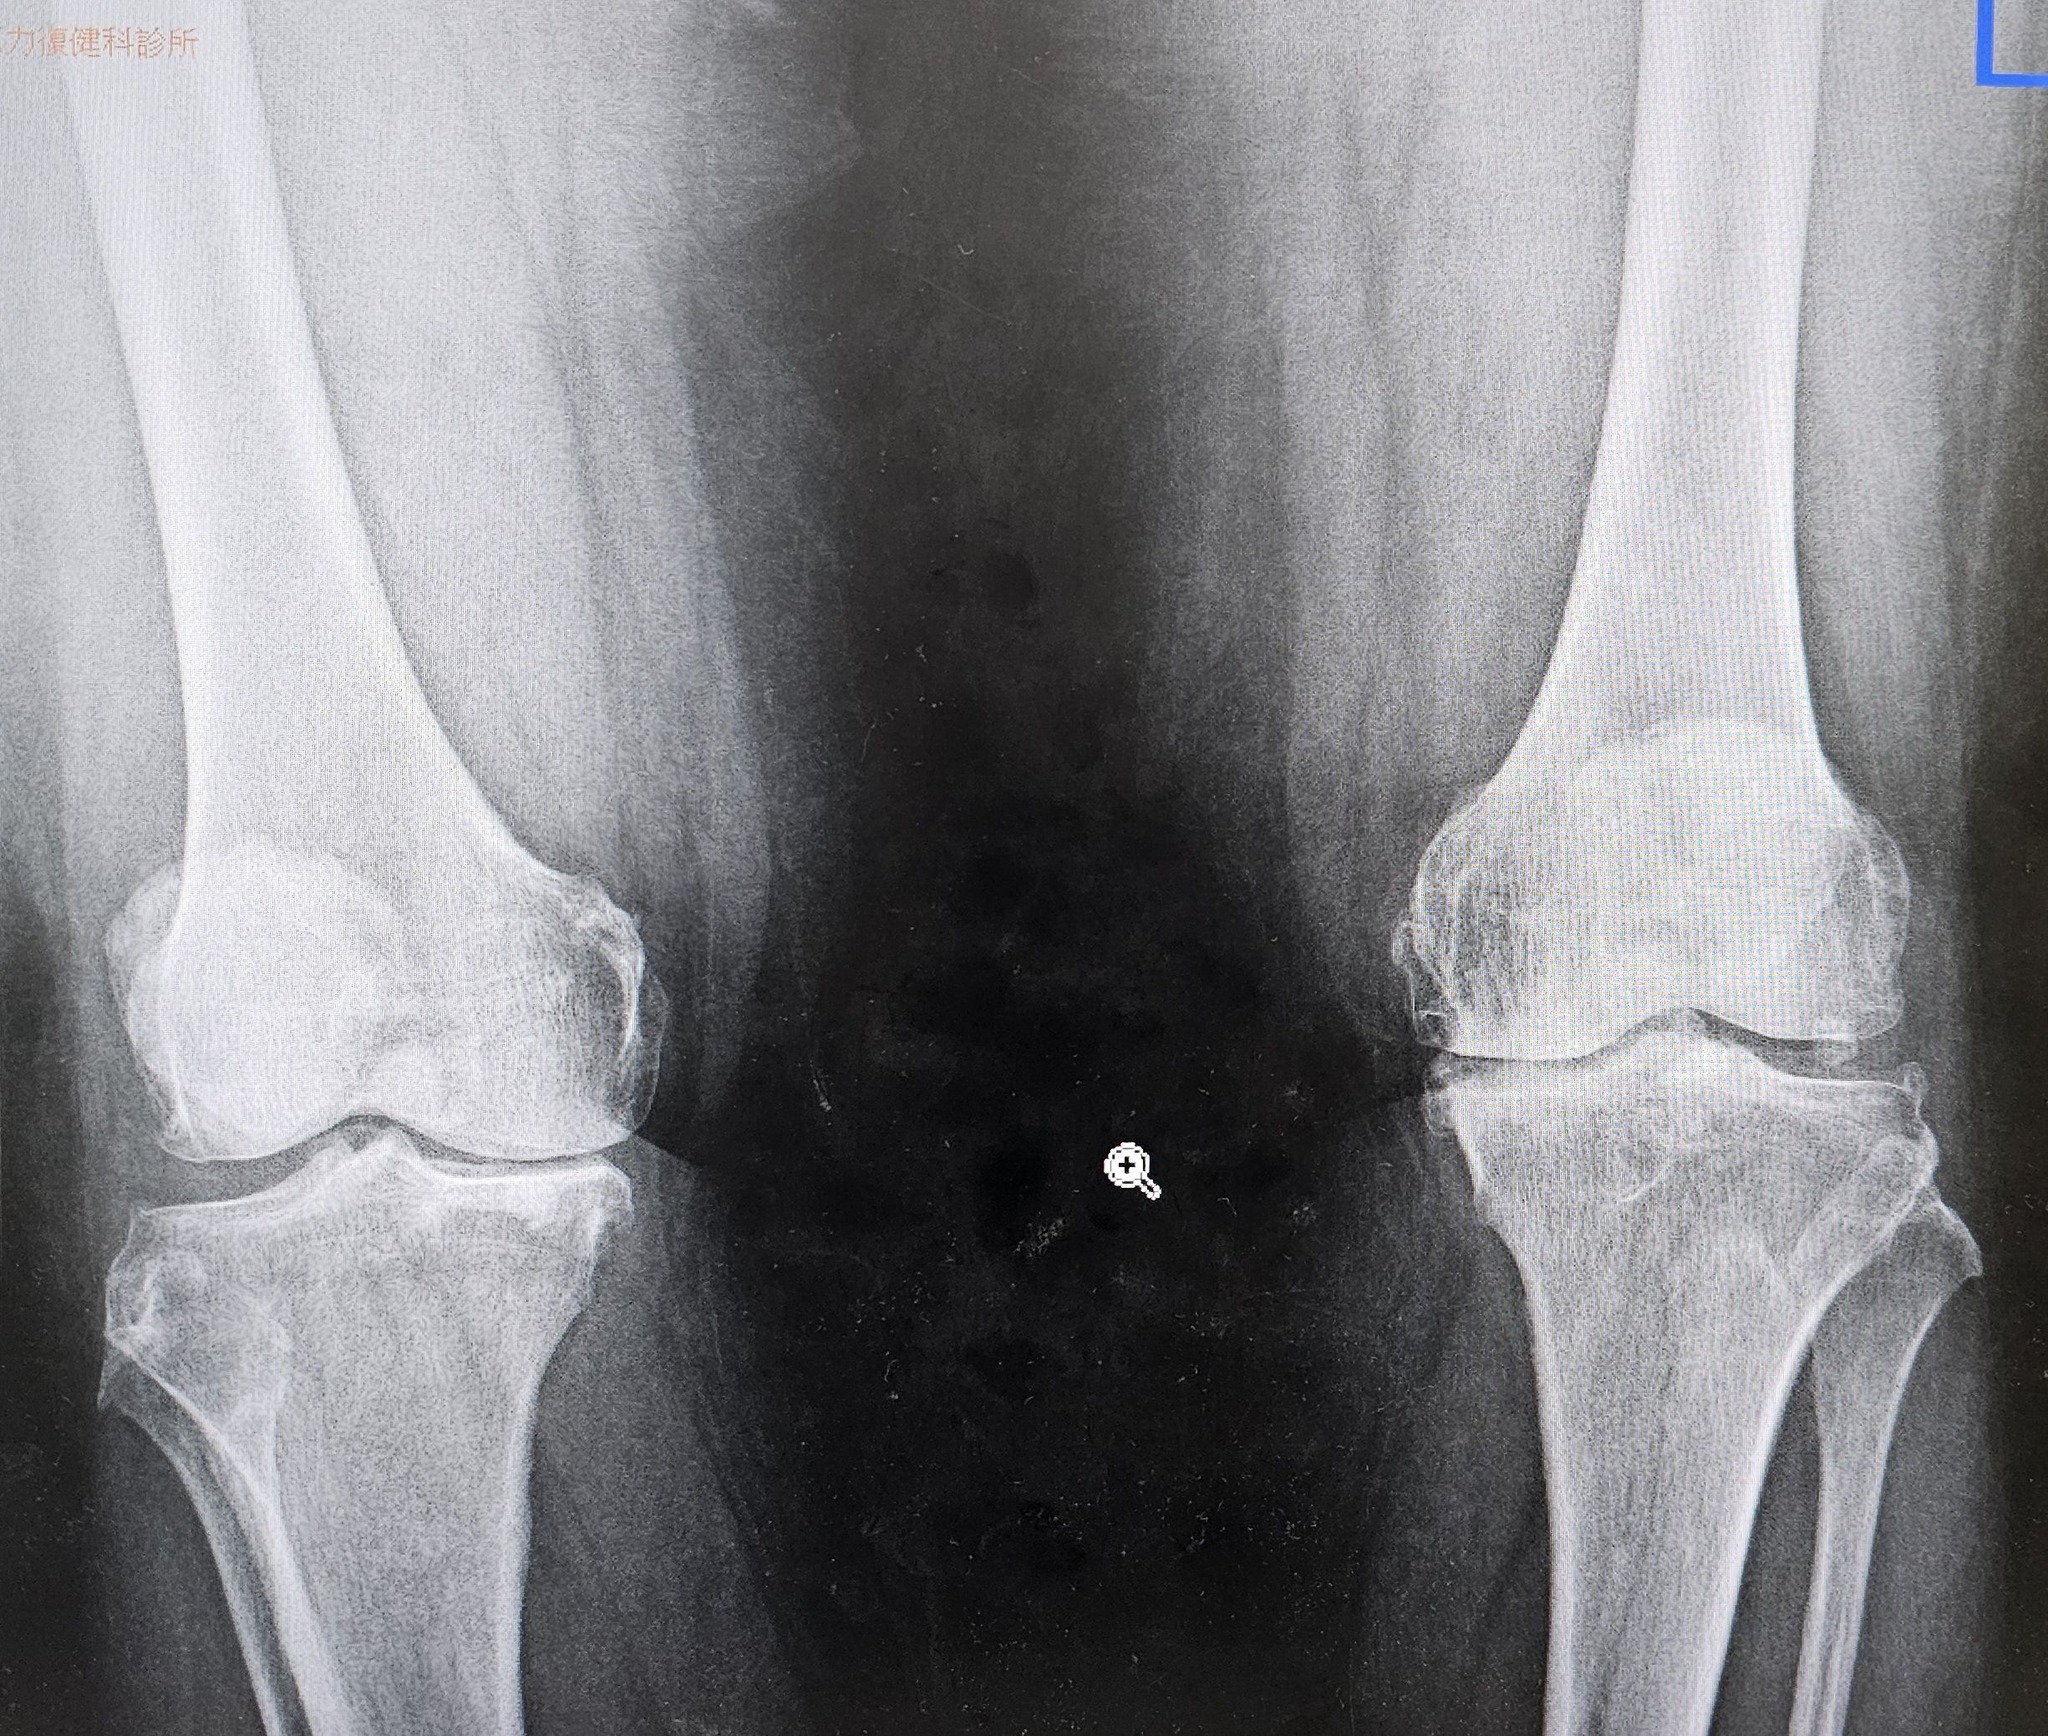

​經過詳細的理學與影像檢查(X光及超音波),我們發現奶奶的雙膝已經到了第二至第三期的退化性關節炎,而且左膝內側有骨刺形成,半月板也出現了明顯的退化。